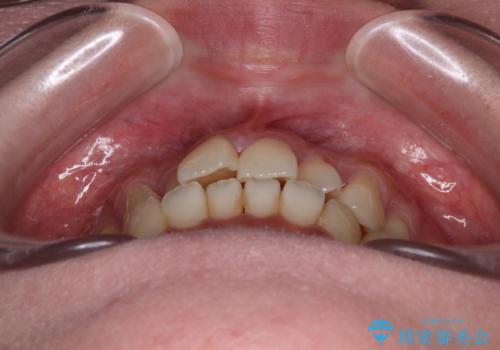

- 上下前歯のデコボコやクロスバイトを気にして来院された患者様です。

上顎歯列が下顎の歯列に対して狭小であり、一部下顎の奥歯が上顎よりも外側に位置している状態でした。

上顎の急速拡大装置を使用して上顎骨を側方に拡大することで上顎歯列を拡大し、下顎歯列も拡大できるようにすることで、歯列を整えることとしました。

歯列矯正では基本的に骨格を改善することはできませんが、急速拡大装置(MARPE)を使用することで上顎骨を側方に拡大させることができ、咬合状態を大きく改善することができます。